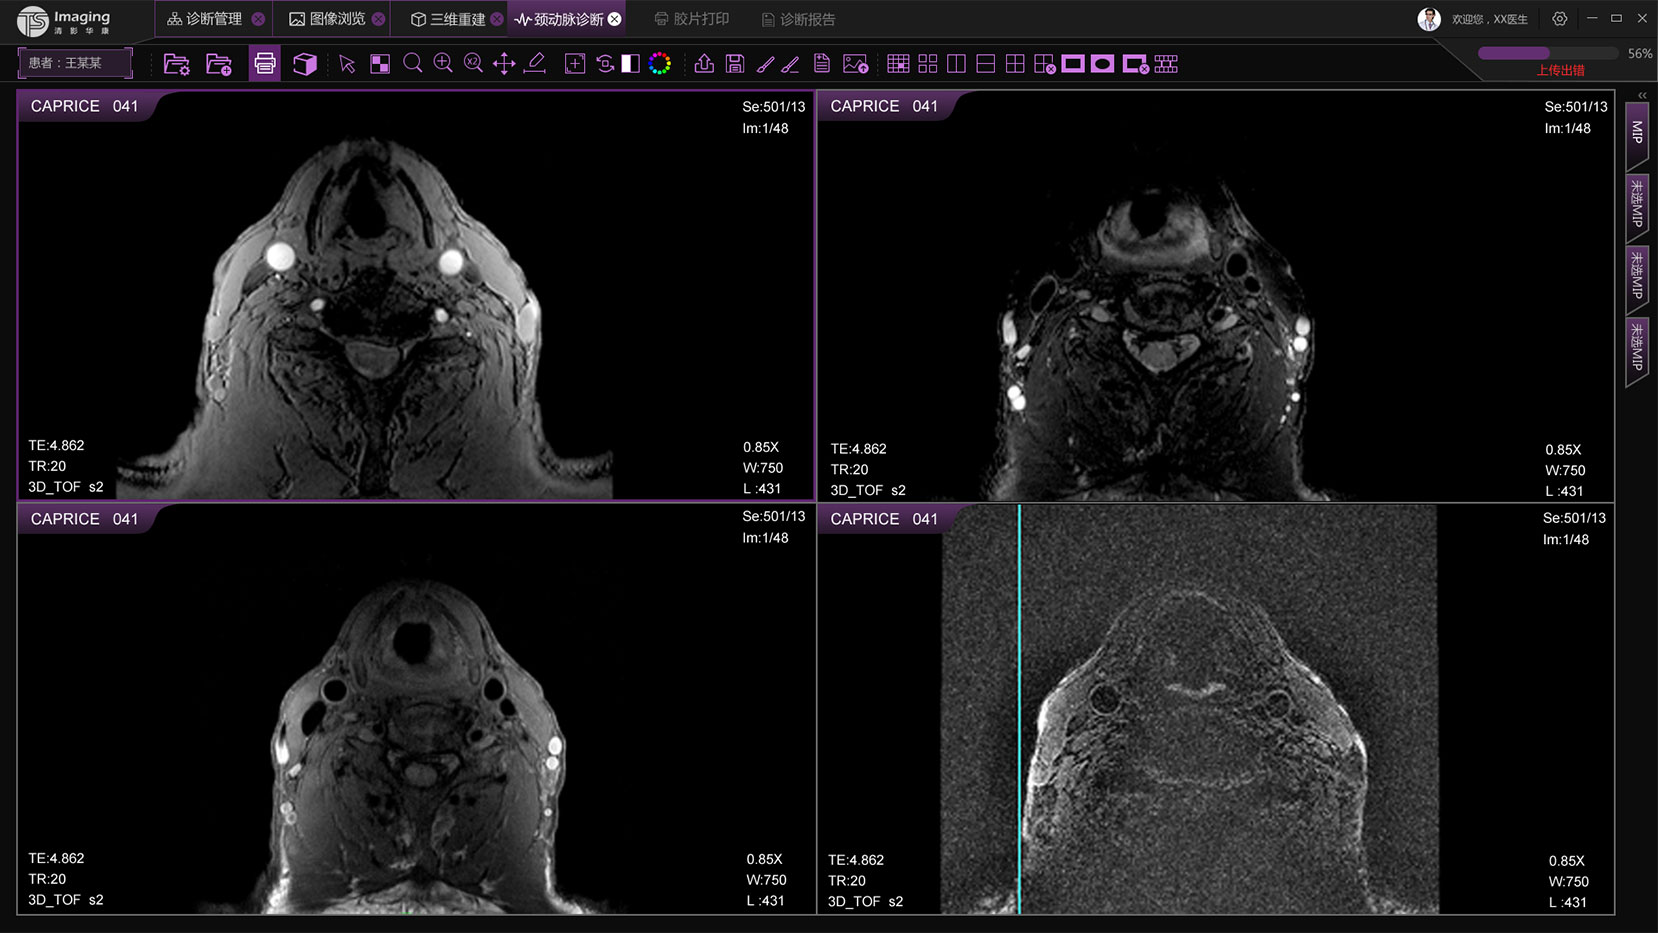

頸動(dòng)脈診斷頁(yè)面

頸動(dòng)脈診斷頁(yè)面整體布局和三維重建比較相似,最大的區(qū)別是右側(cè)的操作區(qū)域,血管分析都為按鍵操作,通過(guò)間隔的大小分成三部分。單層切片除了按鍵還有下拉菜單的操作。